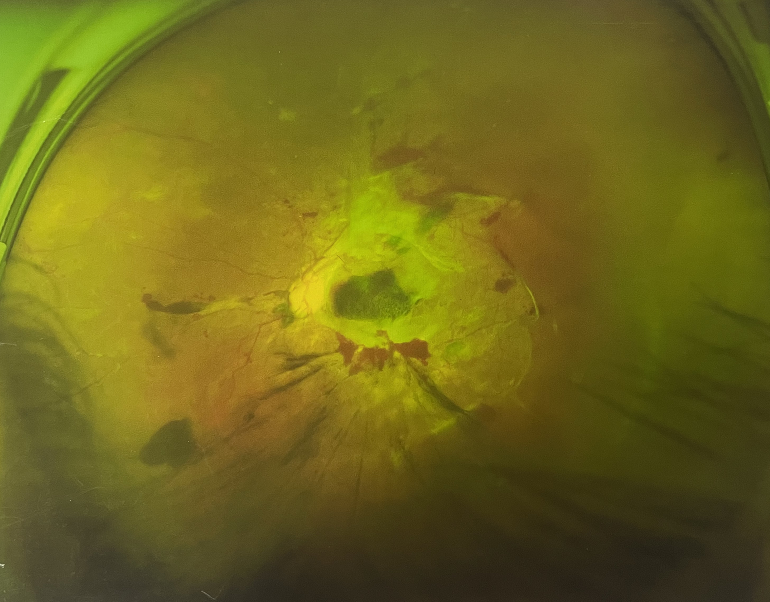

眼底出血一般多久能好?眼底出血可以由眼科本身疾病引起,常見的是視網(wǎng)膜靜脈阻塞、糖尿病視網(wǎng)膜病變、中心性滲出性視網(wǎng)膜病變、視網(wǎng)膜動(dòng)脈硬化、老年性黃斑病變、視網(wǎng)膜靜脈周圍炎。

另外,眼底出血還可以由全身疾病引起,比如糖尿病可以引起眼底出血,高血壓也會(huì)引起眼底出血,還有嚴(yán)重的腎病,血液方面的疾病都可以導(dǎo)致眼底出血。

眼底出血一般多久能好?眼底出血如果是輕癥,時(shí)間較短的患者大約3-6個(gè)月可以恢復(fù),如果是重癥或者病程較長(zhǎng)的患者,可能要持續(xù)1年,甚至2年時(shí)間。

眼底出血一般多久能好?眼底出血是醫(yī)生用檢眼鏡才能看到,患者和其他人看不見。眼底出血不是單獨(dú)的病,一般來(lái)說(shuō)是由眼科本身疾病造成,還可以由全身疾病造成。比如常見的視網(wǎng)膜靜脈阻塞、糖尿病視網(wǎng)膜病變等引起的眼底出血較常見。眼底出血一般多久能好?所以眼底出血的出血吸收時(shí)間也不一樣,要根據(jù)病情輕重決定其預(yù)后,出血吸收時(shí)間也不一樣。